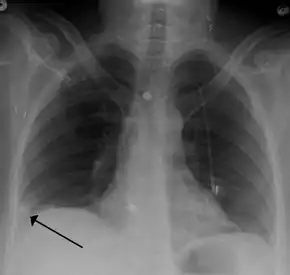

- Pulmonary embolism (white arrow) that have been long-standing and has caused a lung infarction (black arrow) seen as a reverse halo sign.

- Chest X-rays are often done on people with shortness of breath to help rule-out other causes, such as congestive heart failure and rib fracture. Chest X-rays in PE are rarely normal,[59] but usually lack signs that suggest the diagnosis of PE (for example, Westermark sign, Hampton's hump).